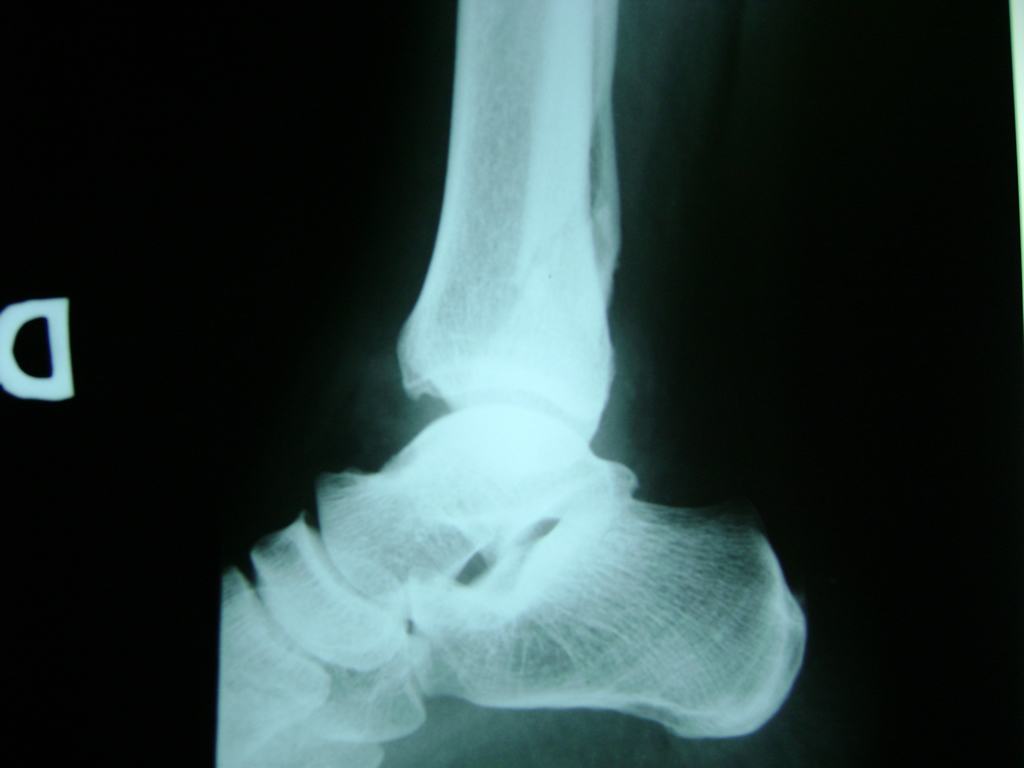

Una fractura de tobillo es la rotura de uno o más de los huesos del tobillo. Estas fracturas pueden ser:

- Producirse en uno o ambos lados del tobillo.

Algunas fracturas de tobillo pueden requerir cirugía si:

- Los extremos de los huesos están desalineados entre sí (desplazados).